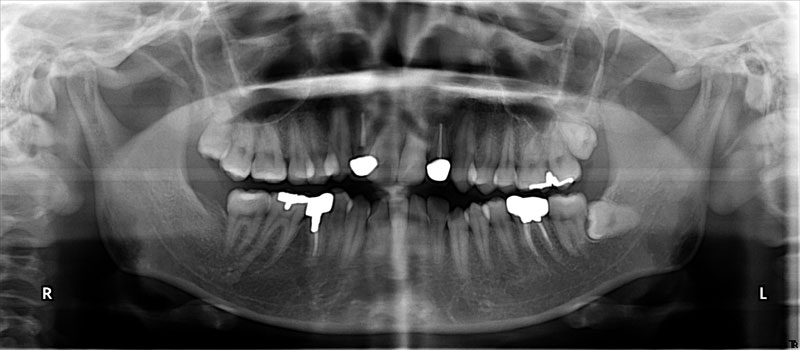

術前

• 初診:2006年、2014年―矯正治療を含めた一口腔単位の治療開始、治療当時、30代女性、非喫煙者

• 主訴:できれば歯並びを良くし歯を白くしたい。

• 治療方針:親知らず3本抜歯、上下小臼歯4本抜歯、矯正用インプラント使用のワイヤー矯正、修復処置、保定(上マウスピース、下ワイヤー)、メンテナンス